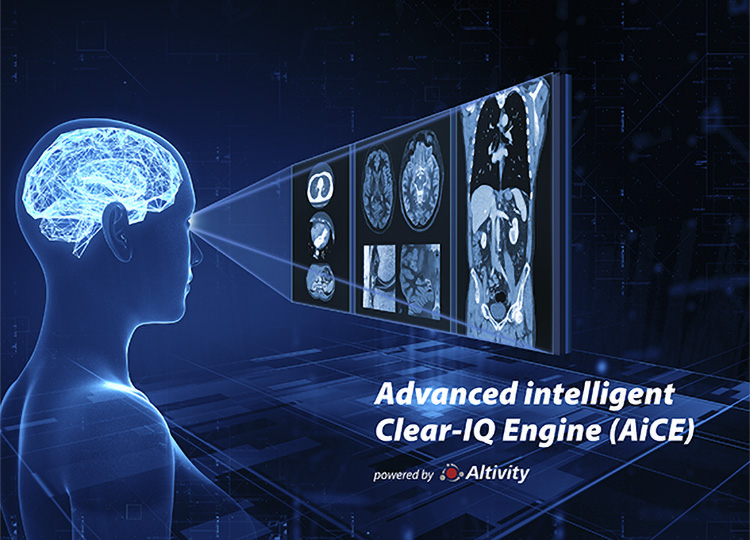

AiCE – четкое изображение при низкой дозе облучения.

Усовершенствованный интеллектуальный механизм Clear-IQ Engine (AiCE) использует технологии глубокого обучения распознования шумов для обеспечения исключительного качества изображения при низкой дозе облучения.

- Низкий уровень шумов

- Естественная текстура изображения

- Четкое разрешение при высокой контрастности

- Четкая распознаваемость при низкой контрастности